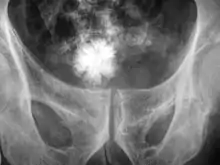

The diagnosis of bladder stone includes urinalysis, ultrasonography, x rays or cystoscopy (inserting a small thin camera into the urethra and viewing the bladder). The intravenous pyelogram can also be used to assess the presence of kidney stones. This test involves injecting a radiocontrast agent which is passed into the urinary system. X-ray images are then obtained every few minutes to determine if there is any obstruction to the contrast as it is excreted into the bladder. Today, intravenous pyelogram has been replaced at many health centers by CT scans. CT scans are more sensitive and can identify very small stones not seen by other tests.[8]

Jackstone calculus

Jackstone calculi are rare bladder stones that have an appearance resembling toy jacks. They are almost always composed of calcium oxalate dihydrate and consist of a dense central core and radiating spicules. They are typically light brown with dark patches and are usually formed in the urinary bladder and rarely in the upper urinary tract. Their appearance on plain radiographs and computed tomography in human patients is usually easily recognizable. Jackstones often must be removed via cystolithotomy.[10]